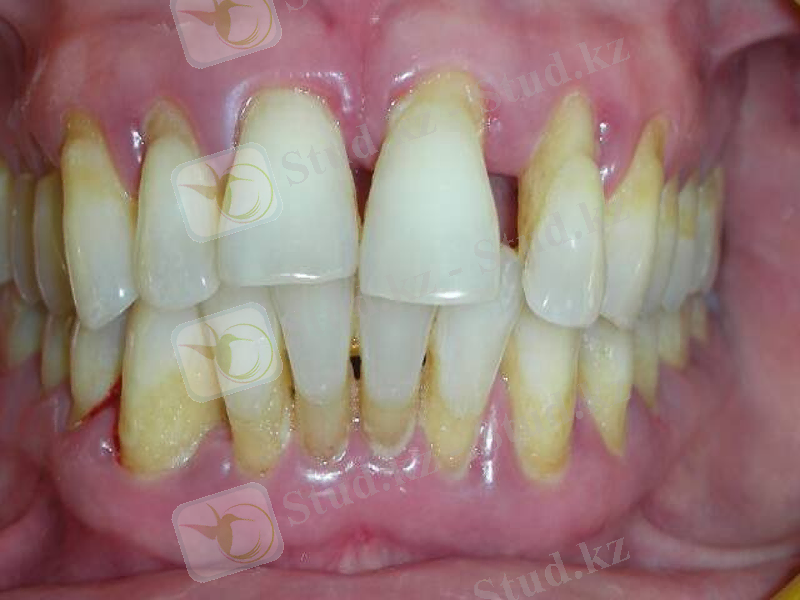

Қарап тексенгенде: Қазылиектің шырышты қабаты цианозданған, ісінген, гиперемирленген. Жұмсақ тіс қақтарын, қызылиек асты және үсті тіс тастарын көреміз. Тістердің мойын бөлігінің жалаңаштануын көреміз.

Сүңгілеу : Тіс аймағында қызылиек байламы бұзылған, қанағыштықтың жеңіл түрі, пародонтальды қалтаның тереңдігі -3, 5 мм-ге дейін болады. Шиллер-Писарев сынамасы -теріс. Қызылиектің шырышты қабаты ашық қоңырдан, қою қоңырға дейін өзгереді.

Қарап тексергенде: Қызылиек көкшіл-қызыл түстенген, бүртіктері мен жиектері қатты домбыққан, тістерге тығыз жанаспаған, қызылиек бүртіктерінің көлемдері әртүрлі болғандықтан оның жиегінің біркелкі иректігі бұзылған. Тістер түбірінің ½ бөлігінің мойын бөлігінің жалаңаштануы.

Сүңгілеп тексергенде сүңгі тиіп кетсе оңай қанайды, периодонттық қалталалардың тереңдігі 4-5мм, қабырғаларын сипап басқанда олардан сарысулы немесе іріңді жалқық бөлінеді.

Шағымы: Тістердің қозғалғыштығына байланысты шайнау кезіндегі қиындығына, тіс түбірінің жалаңаштануына, ауыздағы жағымсыз иіске шағымданады.

Жалпы жағдайы: өзгеріссіз

Қарап тексергенде: Қызылиектің жиегі цианозданған, борпылдақ, ісінген, жергілікті жұқарған, жеке тістердің биффуркациясы жалаңаштанған, түбірдің ½ бөлігінен артық жалаңаштанған. Қызылиек асты және үсті тіс қақтары бар. Тістердің диастемалары, тремалары, жарақаттық окклюзия.

Сүңгілеу кезінде серозды бөліндісі бар, 5мм тереңдікте парадонт қалтасы анықталады, қызылиек жиектеріне күш түсіргенде тіндік детриті бар қалта анықталады, зондылау кезінде қанағыштық анықталады.